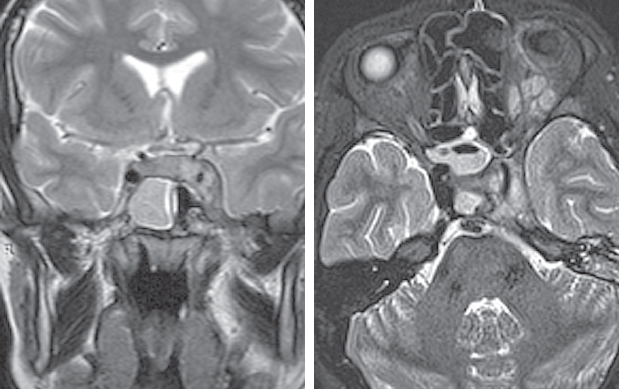

Риногенные внутричерепные осложнения, такие как абсцесс головного мозга и тромбоз вен и синусов головного мозга, по сей день остаются грозной, жизнеугрожающей патологией, не редко заканчивающейся летальным исходом, несмотря на широкое развитие антибактериальной терапии и приверженность пациентов к проводимому лечению. Нередко причиной развития внутричерепных осложнений служит обострение хронического воспалительного процесса в придаточных пазухах носа, тогда как острая ЛОР-патология синусов приводит к развитию риногенных осложнений лишь в небольшом проценте случаев. К сожалению, высокое развитие лучевой и лабораторной диагностики не всегда позволяет вовремя диагностировать данные состояния и оказать адекватную хирургическую помощь. В детском и подростковом возрасте важно выполнить своевременное полное и в то же время малоинвазивное, не приводящее к инвалидизации, хирургическое пособие. Анализ зарубежной литературы последних лет показывает, что нейрохирургические операции в различном объеме (от трепанопункции головного мозга до краниотомии) встречаются в подавляющем большинстве случаев лечения риногенных внутричерепных осложнений. В статье приводятся два клинических случая успешно пролеченных в отделении оториноларингологии Санкт-Петербургского государственного педиатрического медицинского университета пациентов с внутричерепными осложнениями без высокотравматичной нейрохирургической операции. Комбинация эндоназальной эндоскопической операции и массивной адекватной консервативной терапии (антибиотикотерапия в сочетании с применением антикоагулянтов при синус-тромбозе) позволяет добиться выздоровления пациента без обращения к нейрохирургическому вмешательству.